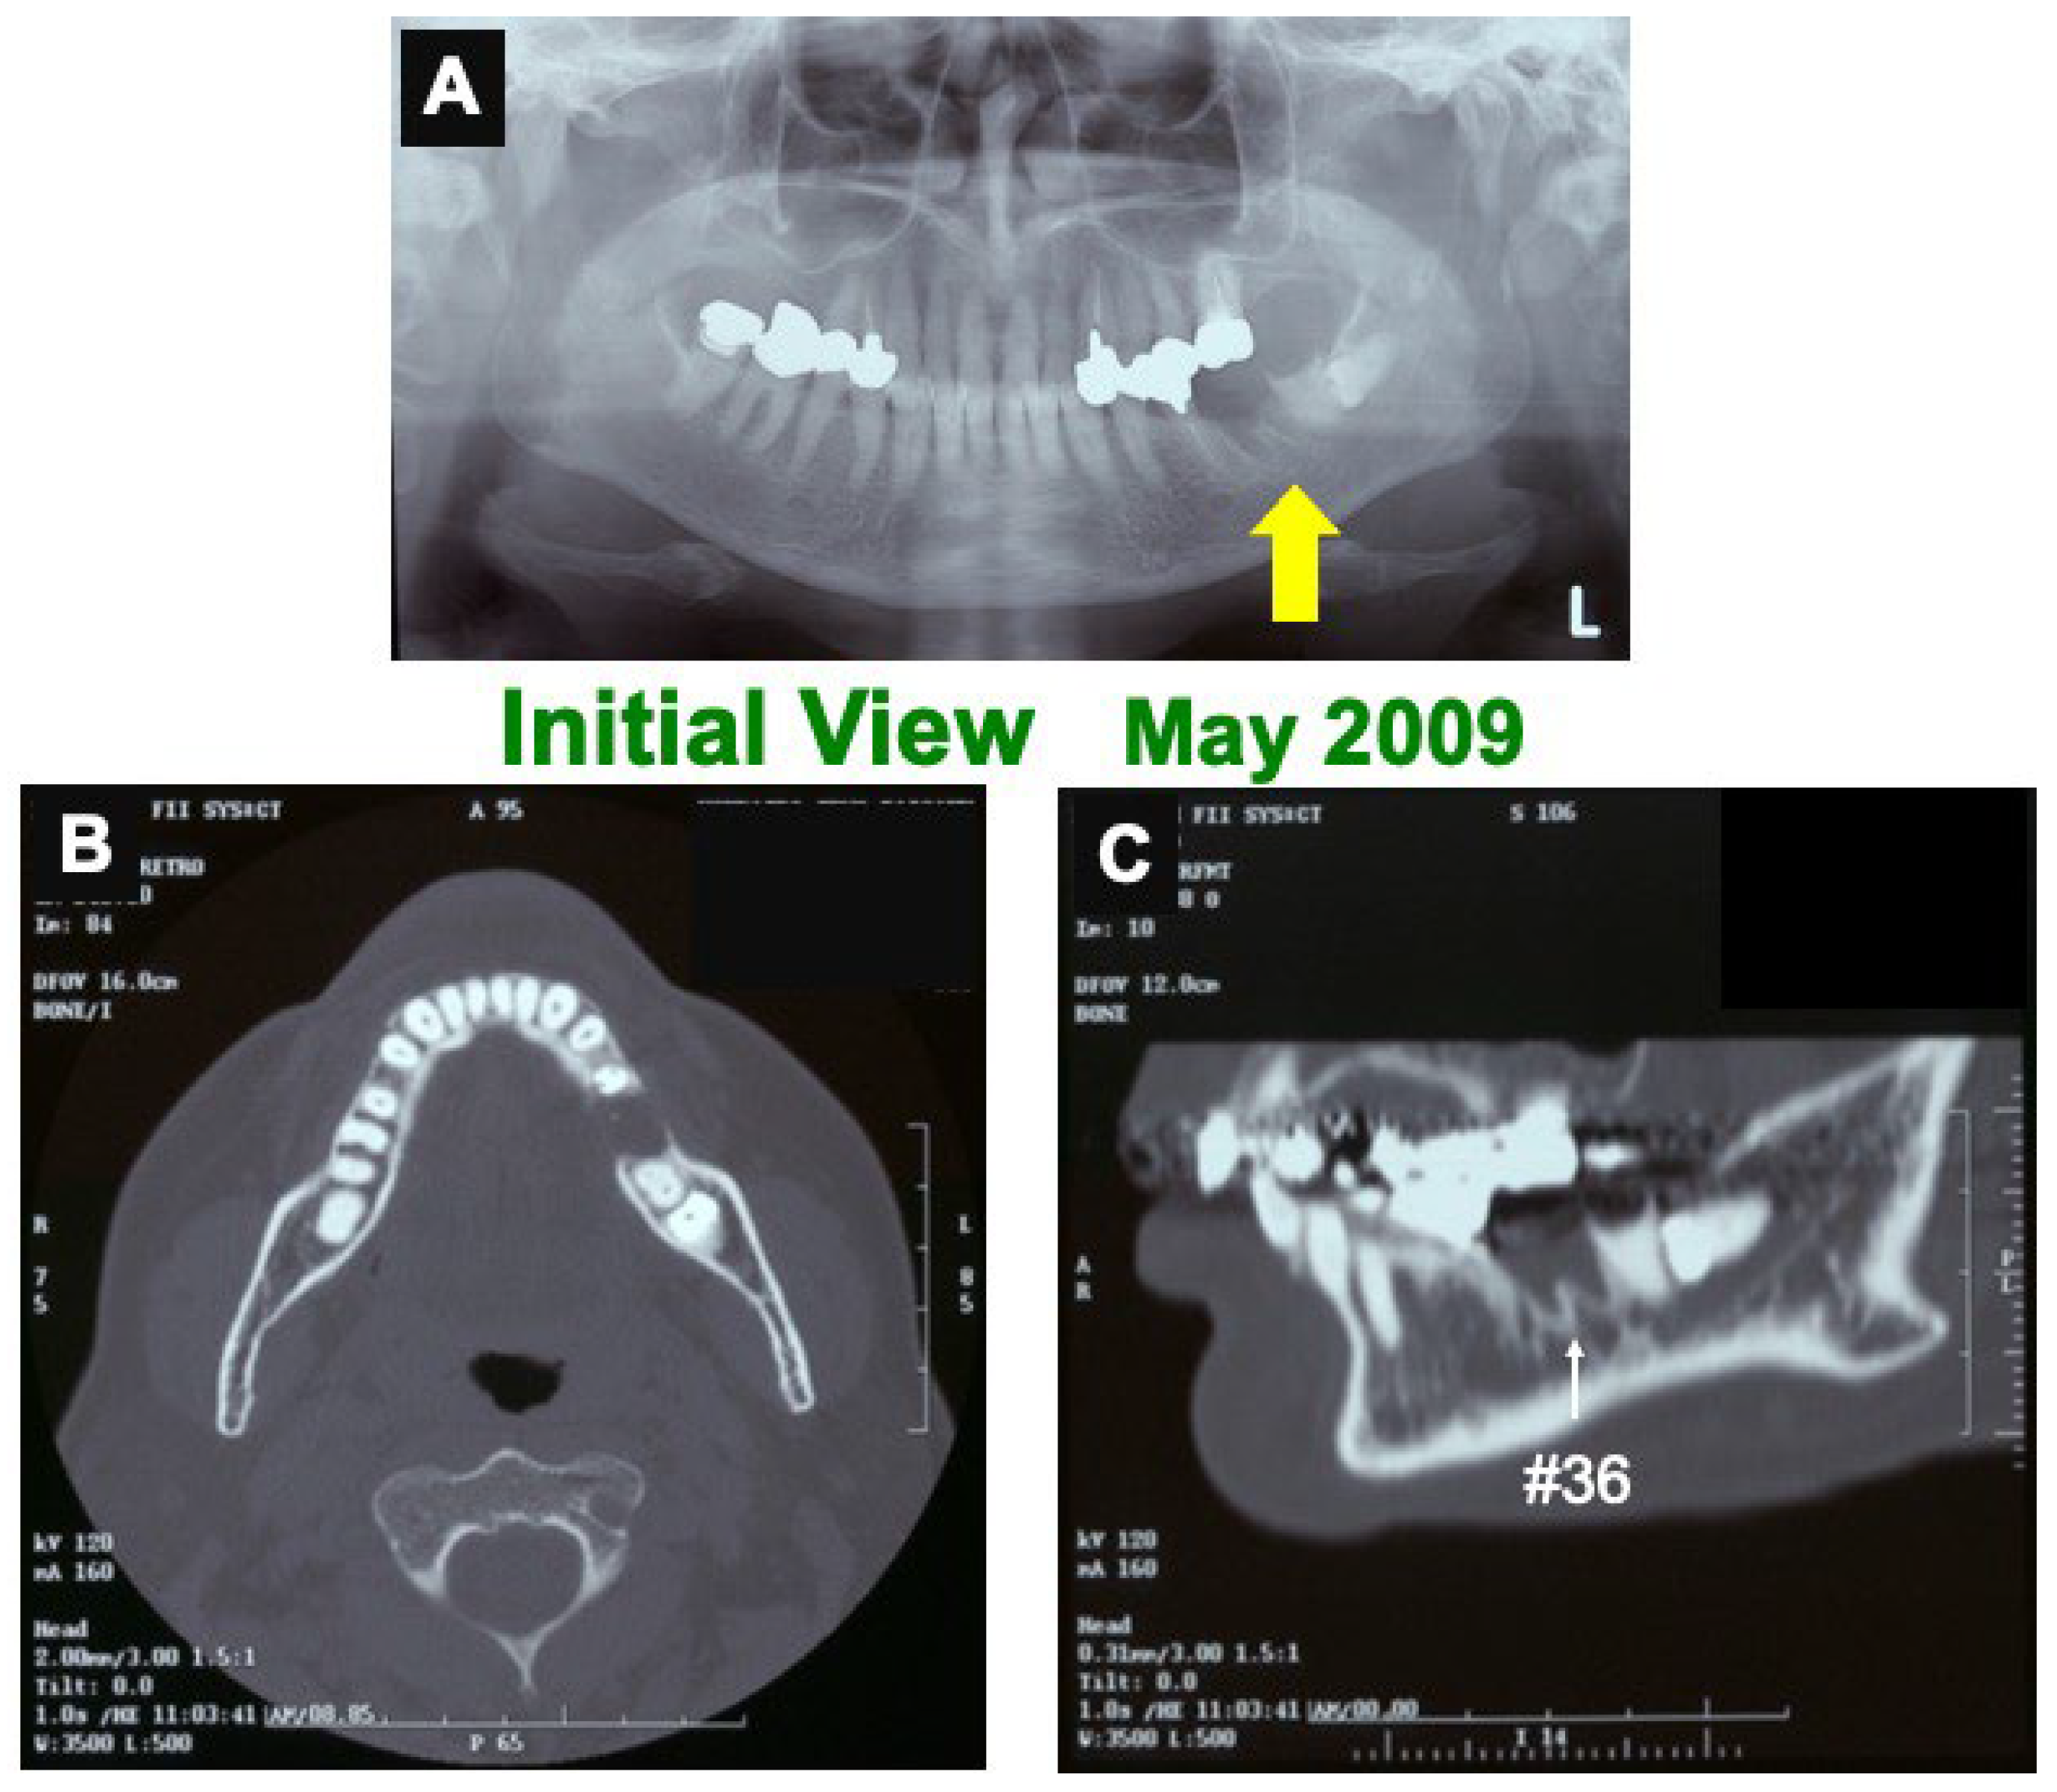

A 66-year-old female presented with healing failure in the extracted cavity (#36) for 2 months after the extraction in a private dental clinic. The patient was introduced to our dental clinic in 2009. Clinical diagnosis revealed healing failure in the socket. Initial X-ray photos showed a clear remaining of lamina dura (#36), a residual root (#37), and a horizontal impaction (#38) (Figure 1). Her medical history was unremarkable.

Figure 1.

Initial views of panoramic X-ray photo (A) and CT (B,C). (A) Arrow indicating clear remaining of lamina dura (#36 socket). (B) Horizontal-axis view showing frame of mandible and non-bony socket (#36). (C) Sagittal-axis view showing sclerotic line (↑) of lamina dura (#36), residual root (#37), and horizontal impaction (#38).

Before the pDDM graft (Surgery 1), the lamina dura (#36) remained clear. (Figure 1A,C). Just after the pDDM graft, pDDM were seen like radio-opaque granules in the treated socket (Figure 3D). At 5 months (Surgery 2), a smooth surface line was seen on the graft site after the opening of mucoperiosteal flap (Figure 4A). The grafted pDDM was harmonized with the mandible, and a bone-like radio-opacity was found in the graft region (Figure 4B). A titanium-fixture was placed properly after the biopsy (Figure 4C,D). The final crown was set (Figure 5A,B) and functionality was well maintained. During the whole follow-up period, a complication, such as marginal bone loss, did not occur (Figure 5C).